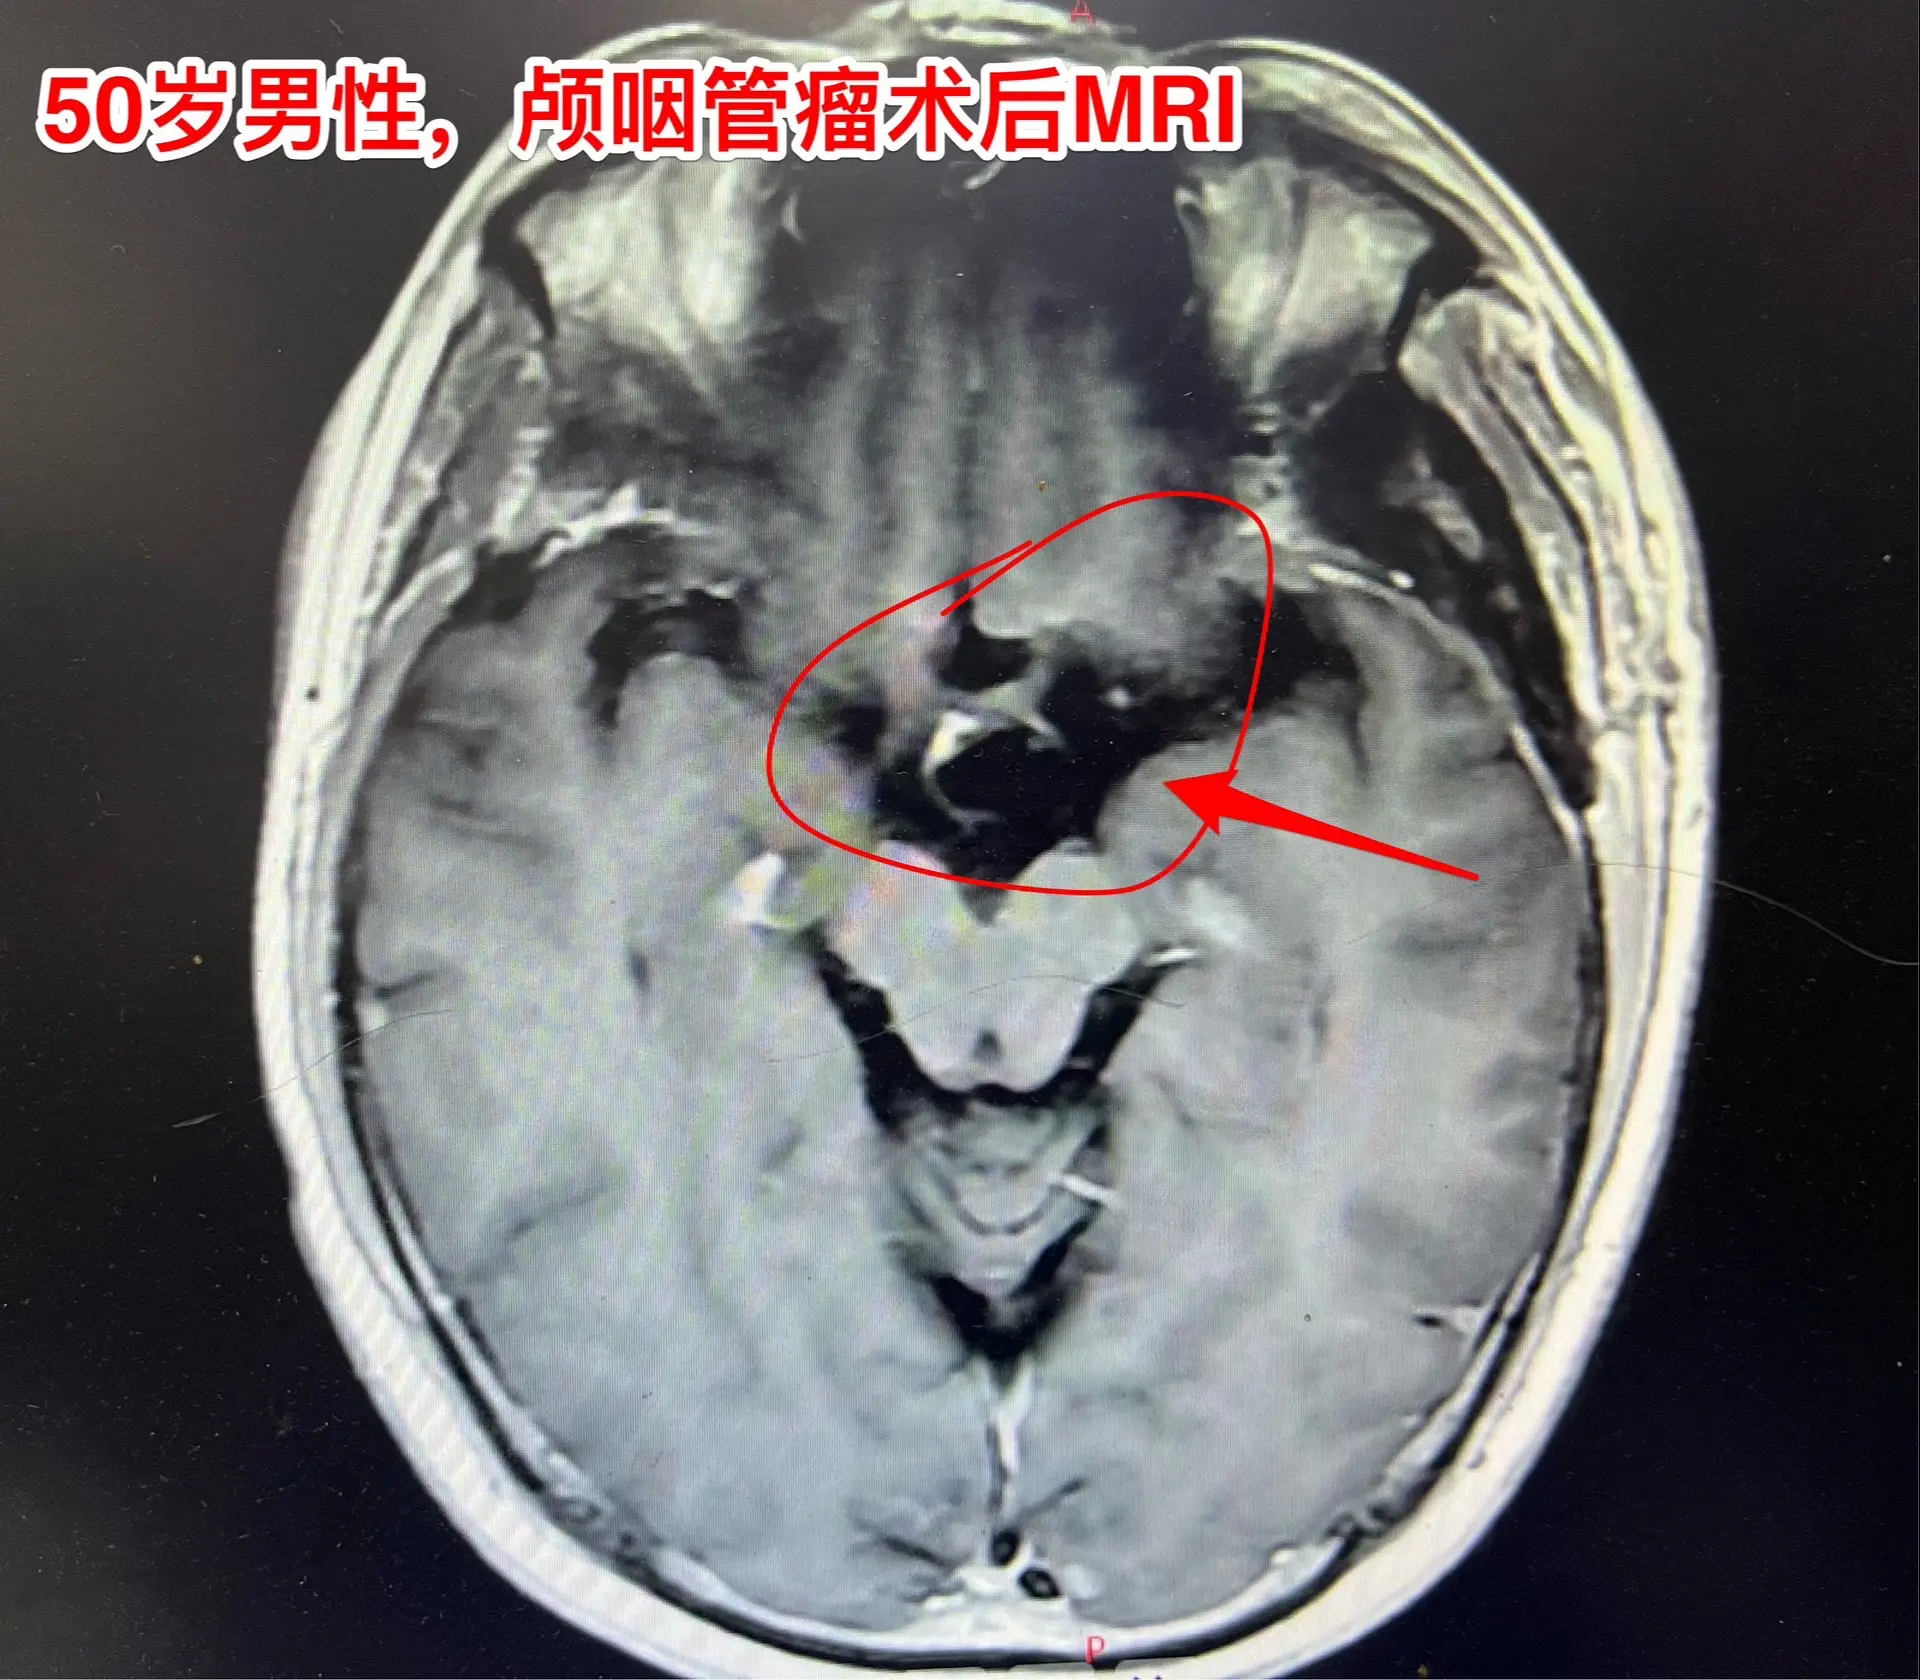

颅咽管瘤手术,出院3天就开车,合适吗?50岁的山东临沂男性,因头痛一年,左眼视力下降三个月于2024.8.16在我科住院。左眼视力0.1,右眼视力1.0。8月22日行开颅手术切除颅咽管瘤,手术后视力改善,身体恢复顺利,9月2日出院了,出院前测左眼视力0.5,右眼1.0。出院时精神好,体力好。 9月8日患者女儿和我联系,说患者出院三天就开车了。我告诉她,需要复查视力和视野,如果视野有缺损,开车是有风险的,不适合开车。